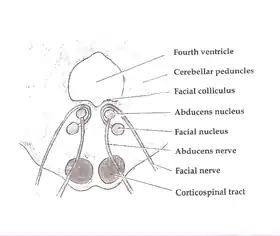

Axial section of the Brainstem (Pons) at the level of the Facial Colliculus (Central tegmental tract not labeled, but region is visible.) | |